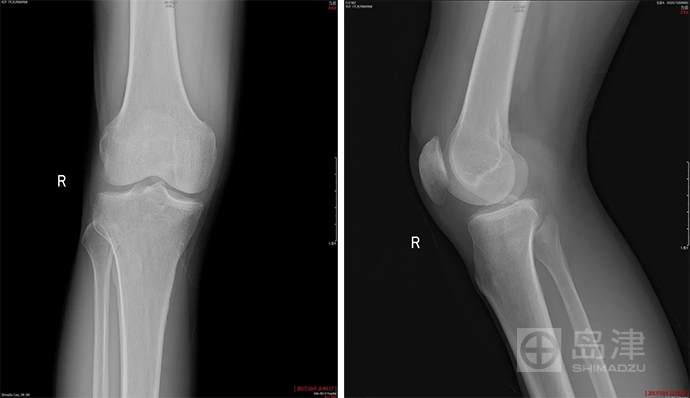

病例三:骨折征象显示

45岁男性,与孩子玩耍时,从一级台阶上蹦下即感右膝疼痛明显,无法行走。

右膝正侧位X线:未见骨折直接及间接征象 。

DTS 显示胫骨平台骨折 。

查 CT MR ,与DTS结果一致。

隐匿性骨折 DR无法发现

右胫骨平台隐匿性骨折

DTS可发现平片无法发现的骨折

CT结果与DTS一致

MRI结果与DTS一致

图像来源:西安市第九医院